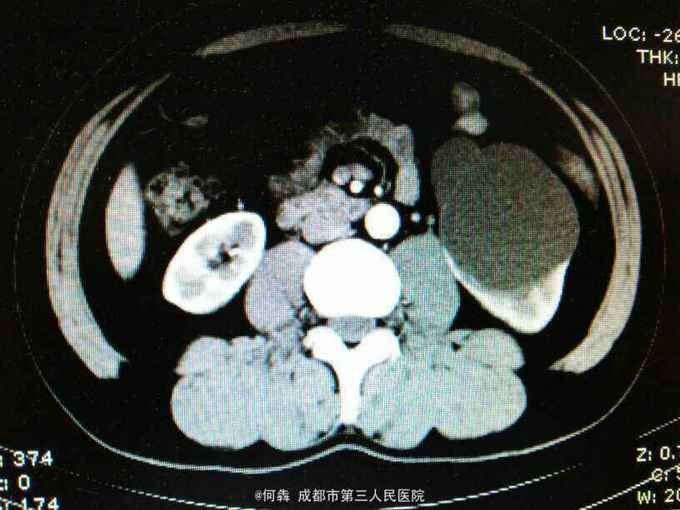

53岁,男性,因“腹腔镜下双肾囊肿切除术后1年余,左腰部窦道形成10月余”入院。无高血压病及糖尿病。

左腰部窦道形成伴少许脓液。窦道脓液培养出绿脓杆菌。

腹腔镜双肾囊肿切除术后窦道形成伴感染。现使用敏感抗生素派拉西林舒巴坦抗感染。